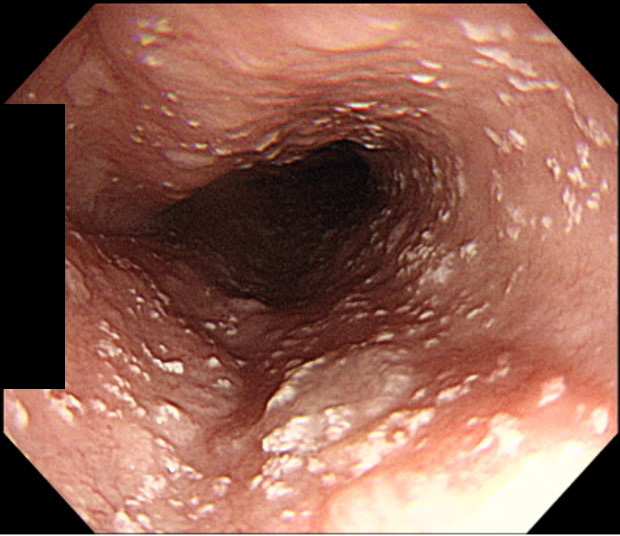

萎縮性胃炎

慢性的な胃粘膜の炎症によって、萎縮が起こっている状態です。原因のほとんどはピロリ菌感染とされており、胃がんリスクが高い状態です。胃がその機能を十分に果たせなくなるため、胸やけ、胃もたれ、腹満感、食欲不振などの症状を起こします。胃カメラ検査で粘膜の状態を直接確認し、組織採取による確定診断やピロリ菌感染検査を行います。ピロリ菌感染陽性だった場合には除菌治療を行います。